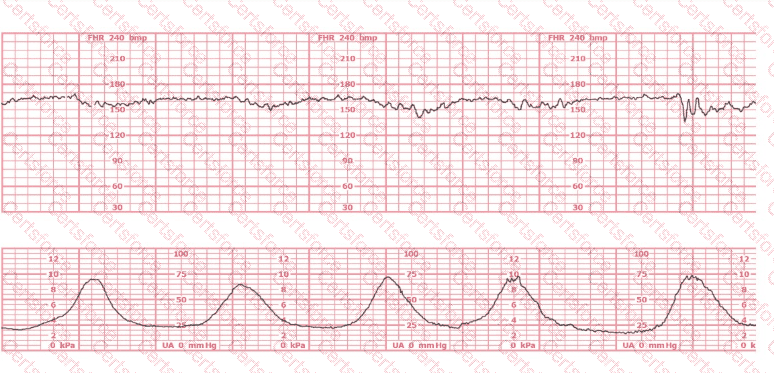

Based on the fetal heart rate tracing shown, the expected fetal pH would be:

Question # 25

Options:

Above 7.15

Below 7.15

Unaffected by the fetal heart rate